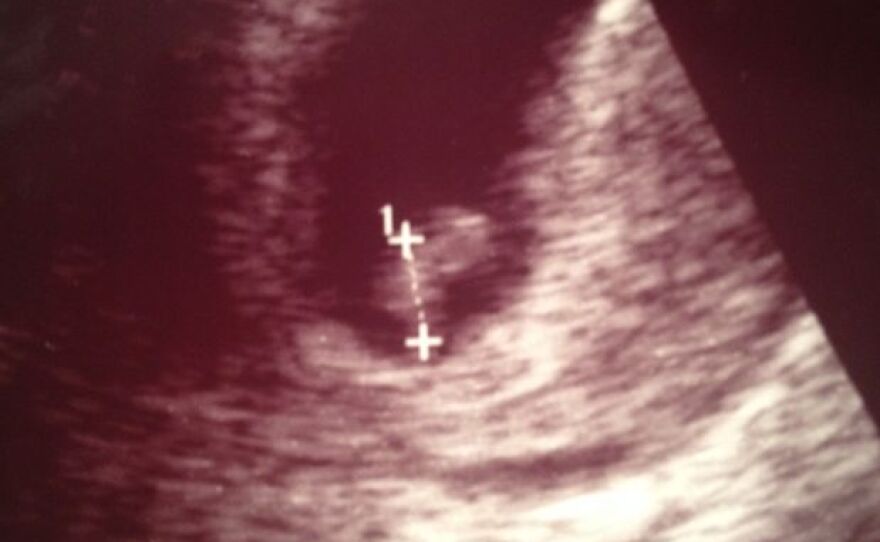

October 25, 2013: This is the very first ultrasound I have of the baby we now call Stella. It was taken a few days after surgery. I'd had two ultrasounds already, but my obstetrician hadn't let me see any images until this one — she didn't want me to get too attached to the idea of a baby until I made it out of the lumpectomy OK. We were still waiting to find out how aggressive the tumor was and whether it had spread. My doctors made me promise to revisit the idea of terminating the pregnancy if the cancer was worse than they expected.